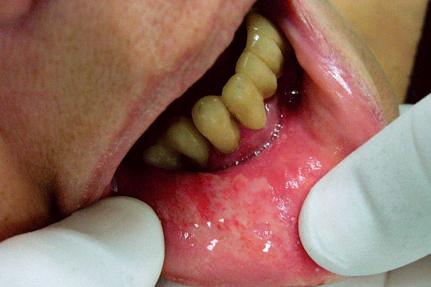

Ulceração

Corresponde à perda de substância aguda ou subaguda com tendência à cicatrização (Fig. 1-20).

Exemplo: trauma protético.

Fig. 1-20. Ulceração localizada em fundo de vestíbulo superior provocada por aparelho protético.